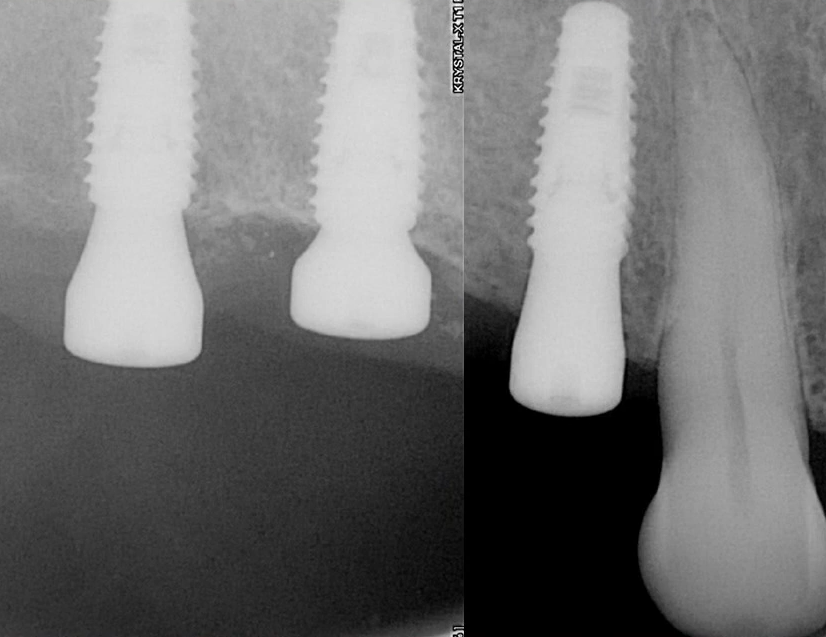

Percussion testing went well; all implants were immobile and produced a sharp, clear sound. The radiograph also revealed no issues.

Radiograph and clinical view after a 6-month break. Youtube/ Implantarium/ Rauf Aliyev

Control radiograph 12 months after restoring the previously mobile implant. YouTube/ Implantarium/ Rauf Aliyev